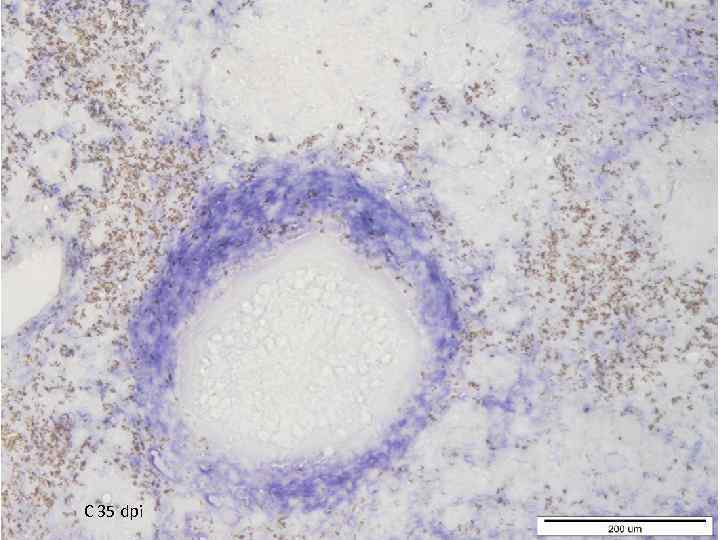

C 35 dpi